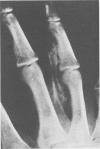

Pressure gun injection injuries are becoming increasingly common. Their effect on the fingers and hands, especially when improperly managed, can be devastating. Therefore it is important to review features, clinical course, anatomic distribution and operative management of such injuries. If a useful hand and fingers are to be attained, rapid and thorough decompression and debridement of these injuries are essential.